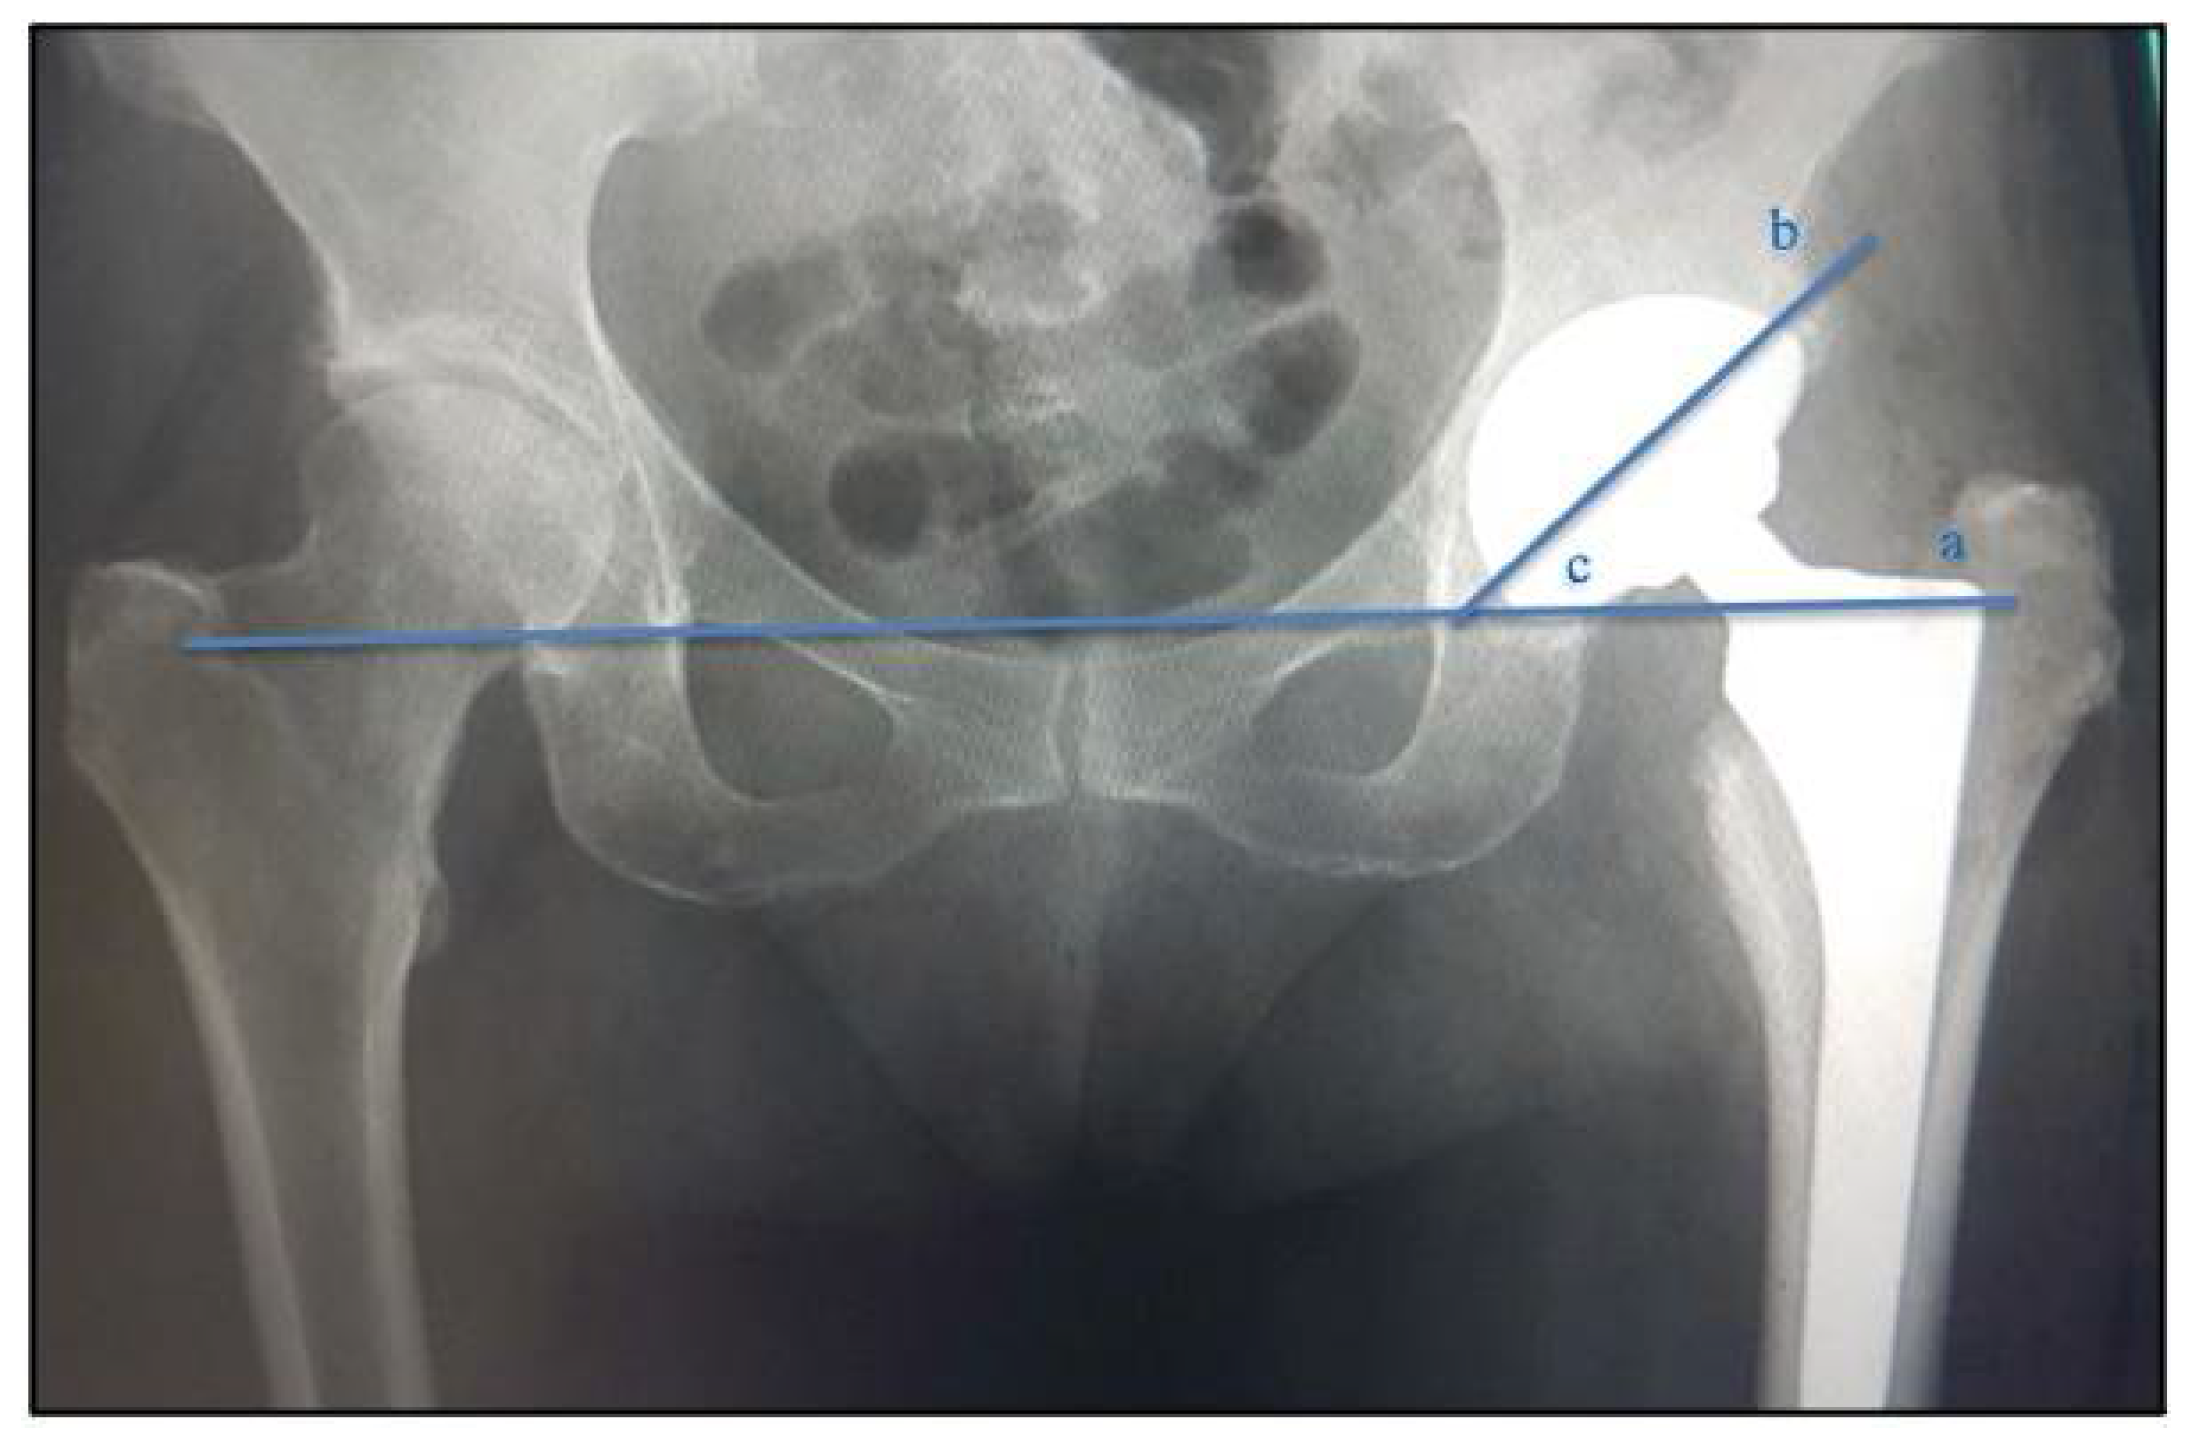

2.3. Analysis of Radiographic Parameters: Positioning and Inclinations of the Acetabular Component

| Acetabular placement (degrees) | 44.3 ± 5.9 | 44.4 ± 6.3 | 0.083 |